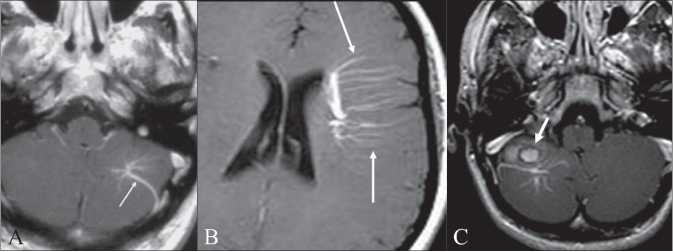

William T. O'Brien, DO 🧠🩻 (@wmobriendo) 's Twitter Profile Photo

#PediNeuroRad #APHPediNeuroRadCase for the Weekend (early) Slide 1: History & images at presentation Slide 2: Annotated images Slide 3: Diagnosis & key points Have a good weekend... #PedsRad #NeuroRad #RadRes #FOAMrad #MedEd

#PediNeuroRad

#APHPediNeuroRadCase for the Weekend (early)

Slide 1: History &amp; images at presentation

Slide 2: Annotated images

Slide 3: Diagnosis &amp; key points

Have a good weekend...

#PedsRad #NeuroRad #RadRes #FOAMrad #MedEd